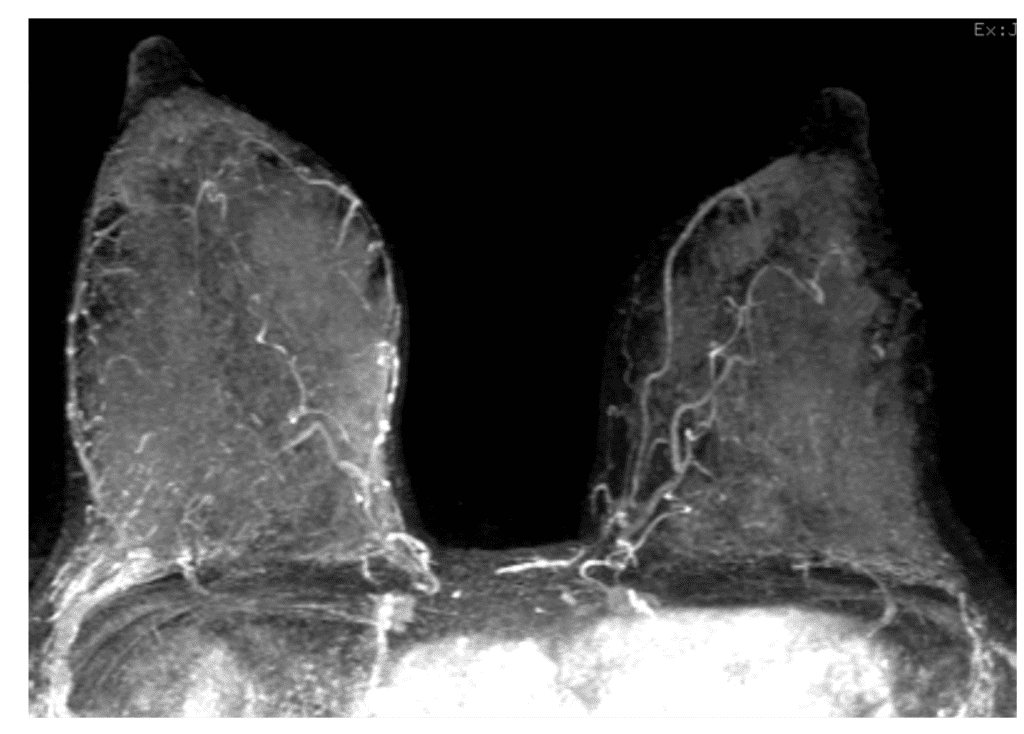

MRI screening during lactation in BRCA I patient

MRI screening during lactation in BRCA I patient.